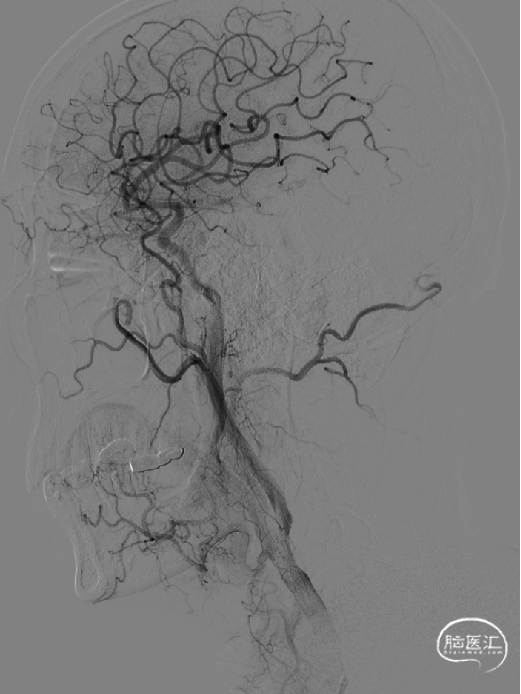

术后正位造影:

小心缓慢释放支架,支架完全释放后手推造影,见支架位置良好,打开较好,原狭窄明显改善,残余狭窄20%。